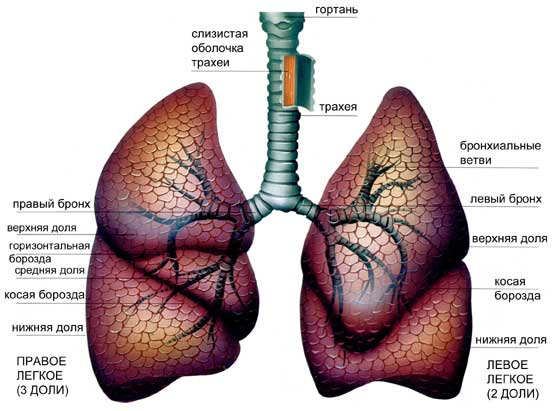

Интерстициальные заболевания легких – это общее название целой группы болезней легких. Объединяет заболевания этой категории то, что все они влияют на интерстиций, часть анатомического строения легких.

Интерстиций, или интерстициальная ткань – это соединительная ткань легких. Интерстиций обеспечивает поддержку альвеолам, микроскопическим воздушным мешочкам легких. Крошечные кровеносные сосуды проходят через интерстиций и выполняют функцию газообмена между кровью и воздухом в легких. Ткань интерстиция настолько тонкая, что она, как правило, не вида на рентгене грудной клетки или при компьютерной томографии, хотя заболевание интерстиция может быть обнаружено при этих исследованиях.

Поражение при интерстициальной пневмонии может быть очаговым или диффузным, а по объему может охватывать целую долю или все легкое.